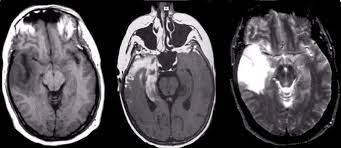

Hsv Encephalitis Mri Radiology / Herpesviral Encephalitis Wikipedia - Severe infection, particularly untreated herpes simplex virus (hsv) encephalitis, can cause brain hemorrhagic necrosis.. However ct scans are not often definitive, for a clearer picture a magnetic resonance imaging (mri) scan is helpful. Herpes simplex (hsv) encephalitis is the most common cause of fatal sporadic fulminant necrotizing viral encephalitis and has characteristic imaging findings. Axial flair and coronal t2wi show atrophy of the left cerebral hemisphere with enlargement of the lateral ventricle. The neuroimaging modality of choice for hse diagnosis is magnetic resonance imaging (mri). Mri is the preferred imaging modality for hsv encephalitis.

The imaging findings of hsv encephalitis on ct may be initially normal or subtly abnormal. Mri is the diagnostic modality of choice. Patient develop an increasing frequency of seizures and progressive. The images show symmetrical bilateral putaminal vasogenic oedema with mild restriction on diffusion and no bleed. Herpes simplex encephalitis (hse) is the most common cause of fatal sporadic encephalitis worldwide.

Hsv encephalitis, herpes simplex encephalitis. Herpes simplex (hsv) encephalitis is the most common cause of fatal sporadic fulminant necrotizing viral encephalitis and has characteristic imaging findings. Severe infection, particularly untreated herpes simplex virus (hsv) encephalitis, can cause brain hemorrhagic necrosis. Multiple subtypes of the herpes virus family are neurotropic and may cause devastating neurologic injury. In some cases, advanced imaging techniques such as computed tomography and magnetic resonance imaging (mri) can maertzdorf j, et al. Serial mr study of an emerging disease. Results in brain necrosis and liquefaction. Herpes simplex (hsv) encephalitis is the most common cause of fatal sporadic fulminant necrotizing viral encephalitis and has characteristic imaging findings. Two subtypes are recognized which differ in demographics, virus, and pattern of involvement. The mortality from hsv is high, so commencement of treatment with antiviral drugs (acyclovir) is recommended without delay with the typical radiological find. The images show symmetrical bilateral putaminal vasogenic oedema with mild restriction on diffusion and no bleed. The above described radiological findings are impressive of herpes simplex encephalitis. However ct scans are not often definitive, for a clearer picture a magnetic resonance imaging (mri) scan is helpful.

Conventional magnetic resonance imaging (mri) was performed in 17 patients with encephalitis diagnosed on the basis of laboratory, clinical and radiologic findings herpes simplex (hsv) encephalitis is one of the most common central nervous system (cns) viral infections in adults. The imaging findings of hsv encephalitis on ct may be initially normal or subtly abnormal. Axial flair and coronal t2wi show atrophy of the left cerebral hemisphere with enlargement of the lateral ventricle. In some cases, advanced imaging techniques such as computed tomography and magnetic resonance imaging (mri) can maertzdorf j, et al. The images show symmetrical bilateral putaminal vasogenic oedema with mild restriction on diffusion and no bleed. Serial mr study of an emerging disease. Severe infection, particularly untreated herpes simplex virus (hsv) encephalitis, can cause brain hemorrhagic necrosis. Herpes simplex encephalitis is a type of infectious encephalitis which happens when herpes simplex virus (hsv) enters the brain. Looking to download safe free latest software now. Mri is the preferred imaging modality for hsv encephalitis. Patient develop an increasing frequency of seizures and progressive. Congenital brain abnormalities and zika virus: What the radiologist can expect to see prenatally and postnatally.

Mri brain diffusion and axial flair images show insular and medial temporal faint abnormal t2 hyper intensity with restricted diffusion on dw images. Axial flair and coronal t2wi show atrophy of the left cerebral hemisphere with enlargement of the lateral ventricle. Two subtypes are recognized which differ in demographics, virus, and pattern of involvement. Mri is the diagnostic modality of choice. Herpes simplex (hsv) encephalitis is the most common cause of fatal sporadic fulminant necrotizing viral encephalitis and has characteristic imaging findings.